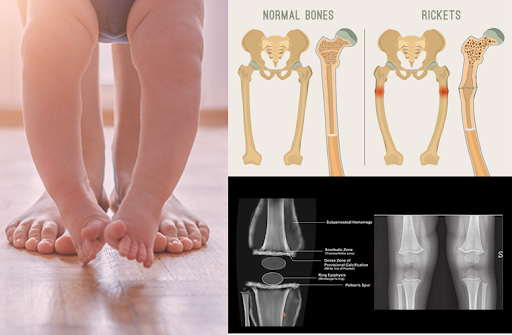

Bowed legs (tangdi mudi)

Knock knees

- Blood tests: Calcium, phosphorus, alkaline phosphatase, vitamin D levels

- X-rays: Show characteristic bone changes of rickets